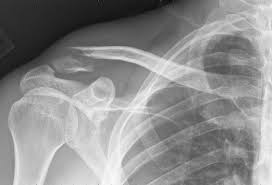

A artrite começa como um processo inflamatório nas articulações, que pode chegar a um quadro sistêmico de febre, lúpus ou problemas renais. “É uma síndrome que evolui para vários órgãos”, explicou o pesquisador. Segundo ele, a doença pode ser desencadeada por razões diferentes como uma infecção viral, bacteriana ou até mesmo estresse.

Por ser uma doença autoimune, o corpo começa a produzir anticorpos e células contra alguns antígenos das articulações, principalmente colágeno e estruturas do tecido. Os tratamentos atuais utilizam anticorpos monoclonais para bloquear a ação de algumas proteínas. “Por exemplo, tem anticorpos que são terapêuticos e bloqueiam a ação de proteínas como a que causa a inflamação”, disse ele.